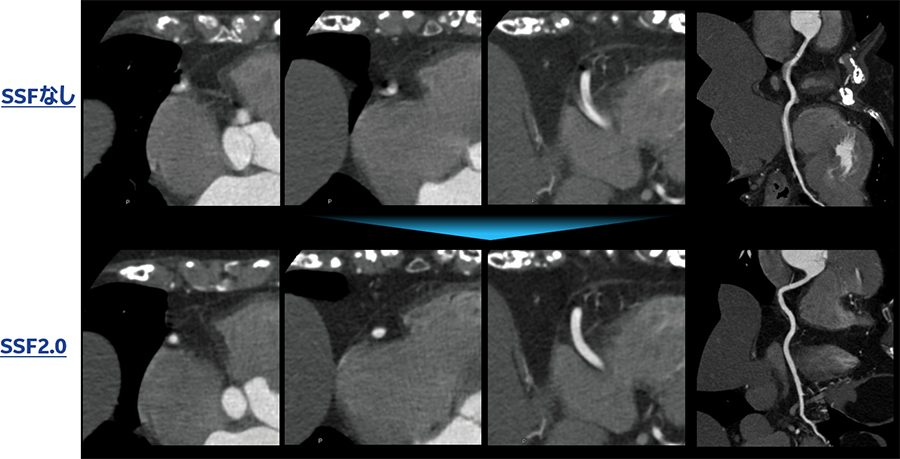

症例2

69歳 女性 心房細動アブレーション術前 βブロッカーなし 撮影時心拍数74~132

rotation time 0.35s/rot pitch 0.16 心位相45% ECG edit

ECG Editor後、(装置が示す心拍変動20%以上の部分のみを抜いた) SSFなし、SSF2.0の比較

Asend_YokohamaSougou_12.jpg

SSF2.0導入前はEdit後に位相探索が必要であったが、SSF2導入後は位相探索が不要であった。